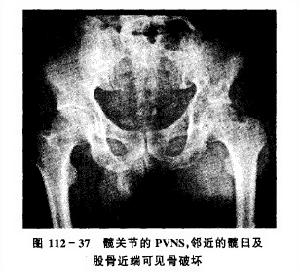

3.PVNS的X線片表現取決於病變的部位

手部的結節型PVNS可以表現為軟組織腫脹和骨侵襲。骨破壞區有邊界清楚的硬化緣,這種骨破壞是病變直接蔓延壓迫鄰近骨造成的結果,而並不提示惡性。